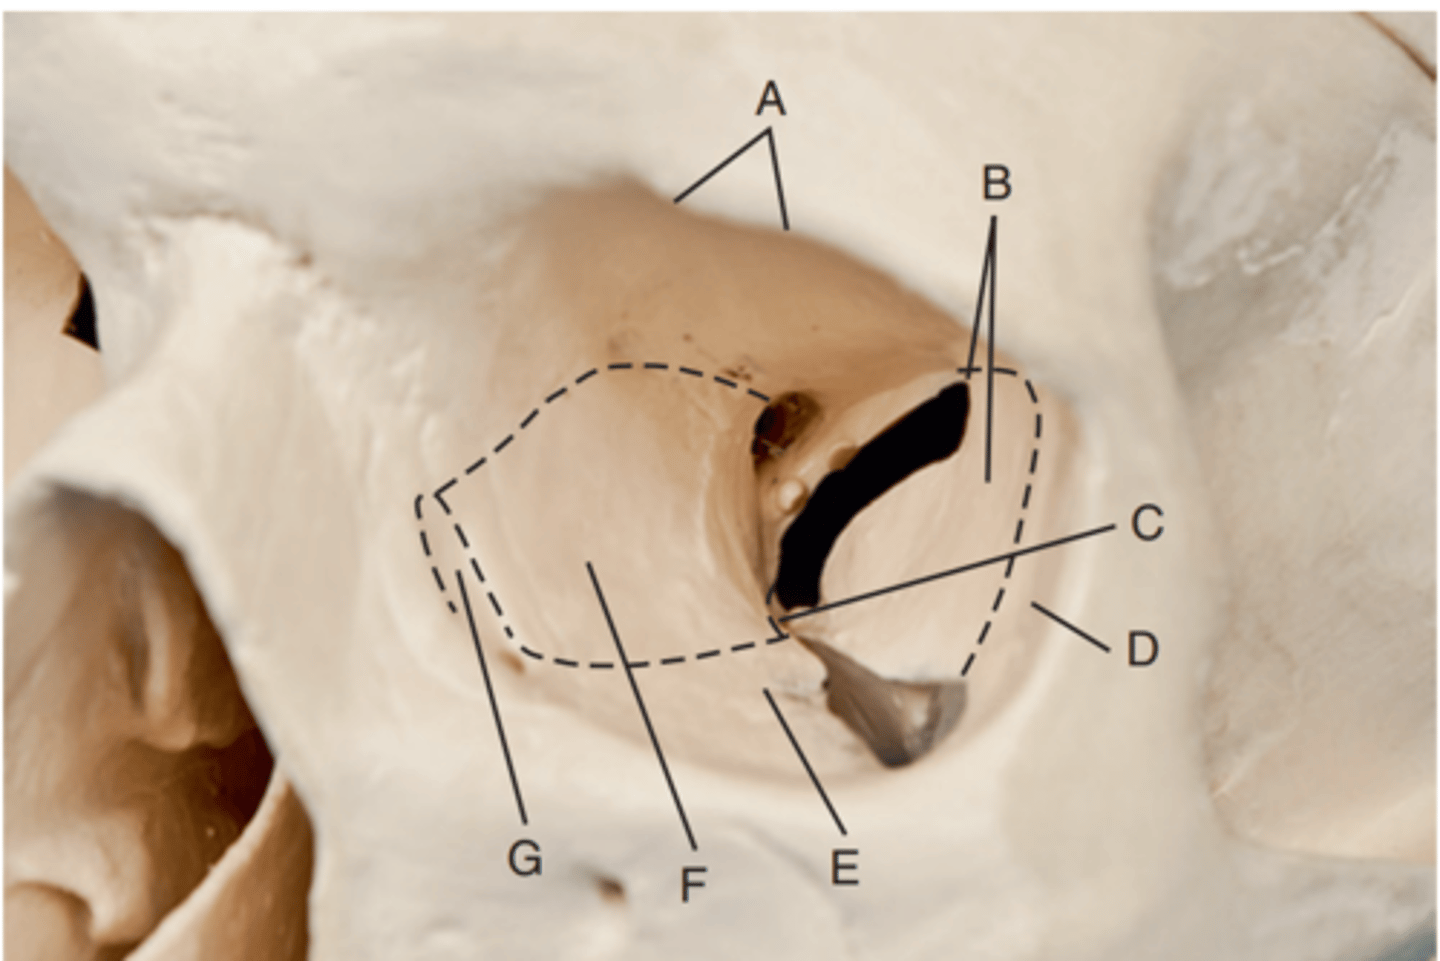

Optic foramen

Label A

Sphenoid strut

Label B

Superior orbital fissure

Label C

Inferior orbital fissure

Label D

Orbital plate of frontal bone

Label A

Sphenoid bone

Label B

Optic foramen and canal

Label C

Superior orbital fissure

Label D

Infraorbital margin (IOM)

Label E

Sphenoid strut

Label F

Lateral orbital margin

Label G

Supraorbital margin

Label H